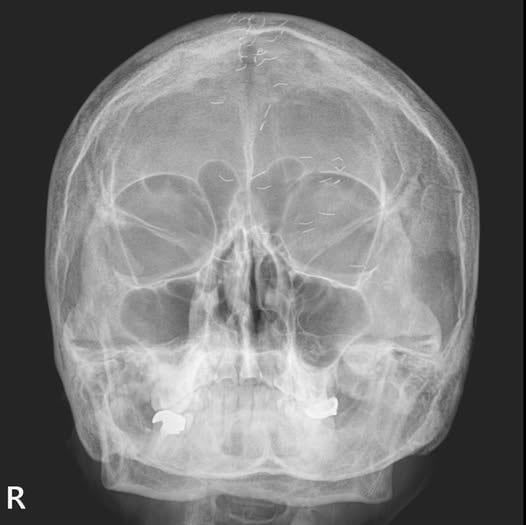

60대 한국 여성의 머릿속에 기생충처럼 보이는 실선이 수십 개 퍼져있는 엑스레이 사진이 공개돼 주목받고 있다. 이물질의 정체는 '금침 요법의 흔적'이었다.

가정의학과 전문의 양성관씨는 최근 자신의 사회관계망서비스(SNS)에 '한국형 진료'라는 제목의 글과 함께 두통으로 양씨를 찾은 60대 여성 환자 A씨의 머리 엑스레이 사진 한 장을 올렸다.

양씨는 "환자 엑스레이에서 1㎝ 크기의 수많은 이물질이 보였다"며 "기생충? 전기칩? 외국이었다면 특이한 환자 사례를 올리는 '케이스 리포트'에 해당하는 사진"이라고 했다. 이어 "하지만 한국 의사라면 보자마자 헛웃음부터 짓는다"며 "저 이물질은 기생충이나 전기선이 아니라 금침 자국"이라고 밝혔다.

양씨는 "(금침 요법 흔적은) 주로 무릎이나 허리 등에서 자주 볼 수 있지만, 이번엔 머리에서 보였다"며 "진단은 저 사진 한 장만으로 내릴 수 있었다"고 했다. 금침이 정수리 부분에 국한되었기 때문이다. 양씨가 환자에 내린 진단은 '긴장성 두통'이었다.